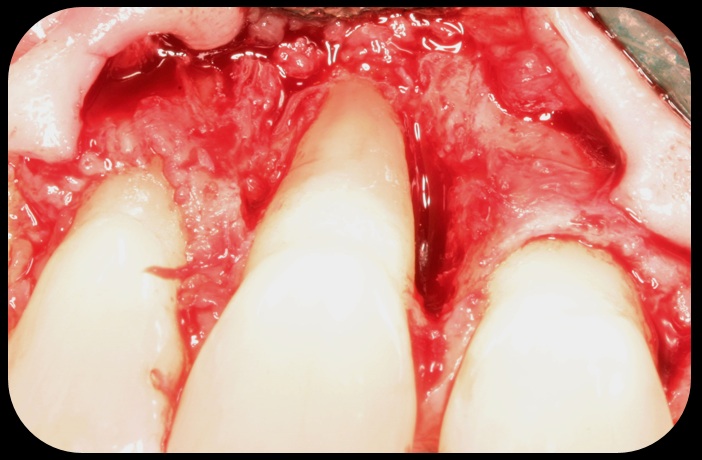

Severe periodontitis lesion.

Fig. 2

Then, too, are opportunities to prepare the site for regeneration by coupling therapies, applying an enamel matrix derivative, along with traditional bone grafts of demineralized freeze-dried bone allograft; potentially, gains in attachment with minimal probing depth and retained papilla may avoid the need for an implant (Figure 2 through Figure 7).